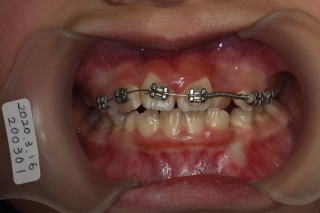

2020年05月25日

反対咬合改善

2020-08-24

状態良好

顎の骨が大きくなれば歯は自然ときれいに並んできます。